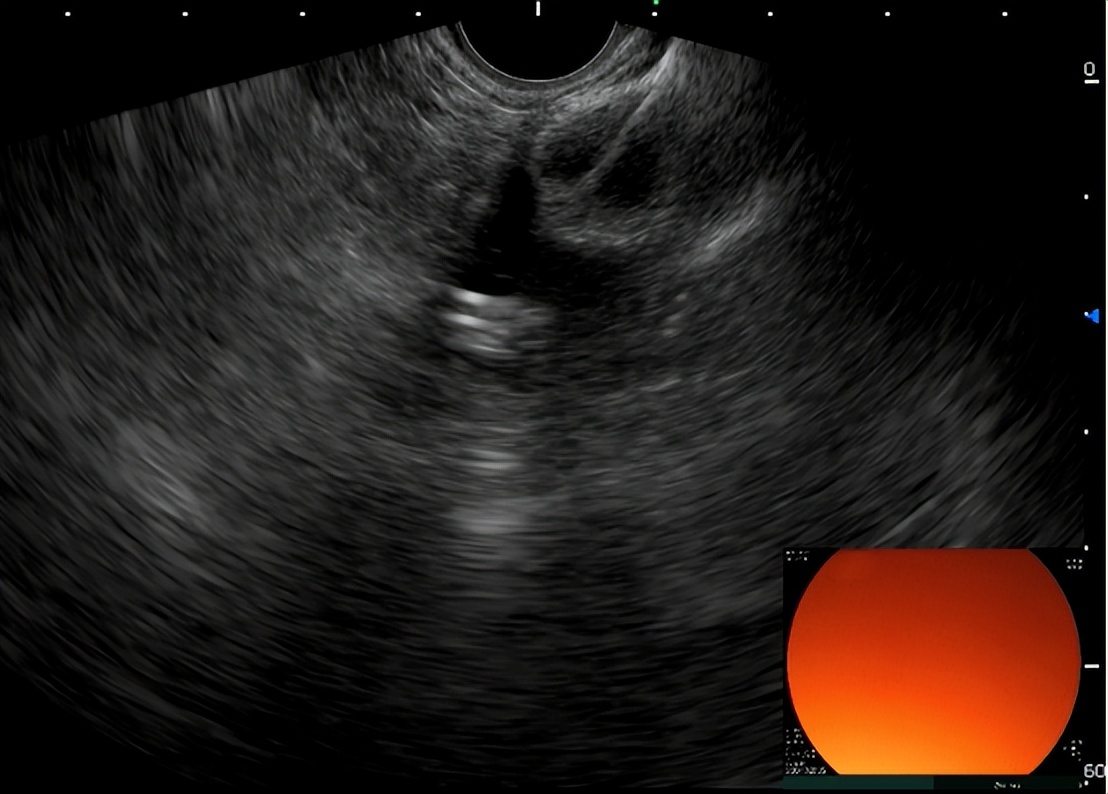

超声引导下置入胃空肠支架

胃空肠支架置入后观察